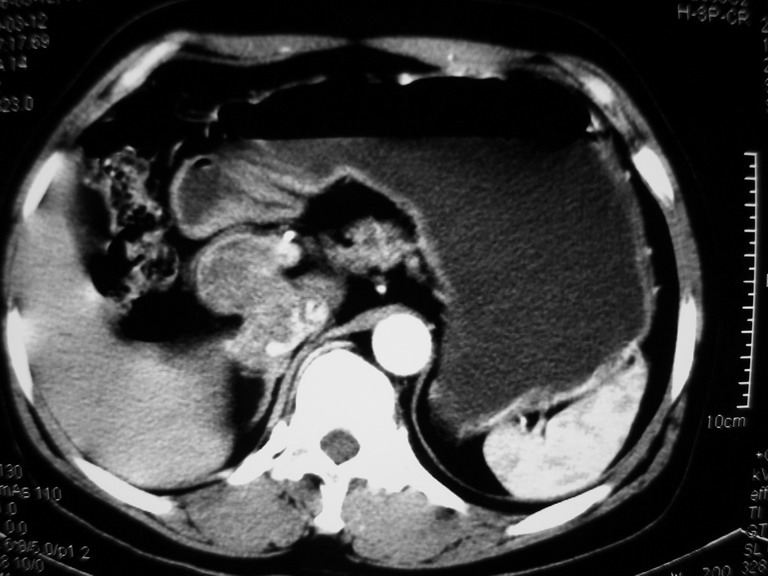

患者,女性50岁,上腹部不适2年余,既往多次腹部彩超未见异常,今日上午在我院查彩超发现肝右叶囊实性病变,外院辅助检查,afp,cea,ca199, 都在正常范围内,无肝炎史否认肿瘤史,生活在牧区

接着往下一贴看,有静脉期和延迟期,在看看和下腔静脉及十二指肠的关系,腔静脉内是不是栓子?

考虑肝右叶与尾叶交界区肝癌(部分外生),侵犯下腔静脉并下腔静脉瘤栓形成。

肝包虫病可能性大